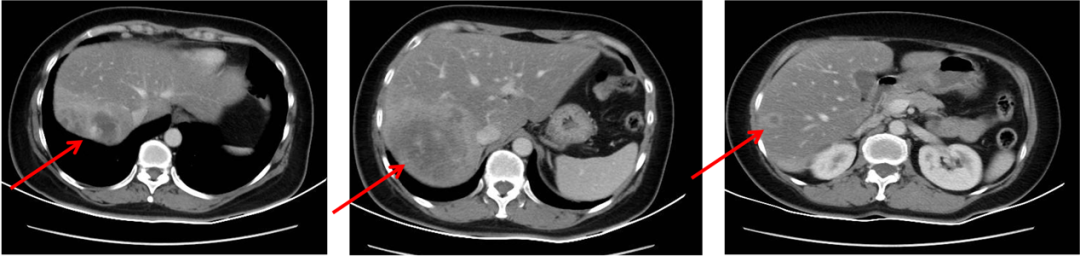

▌影像学检查:

2013年6月30日腹部CT:肝右后叶病灶并肝内多发子灶,考虑M,病灶总范围8.0*5.8cm,其病灶周围可见多发异常廓清子灶(4-5个),最大约1.6cm;

图1. 腹部CT